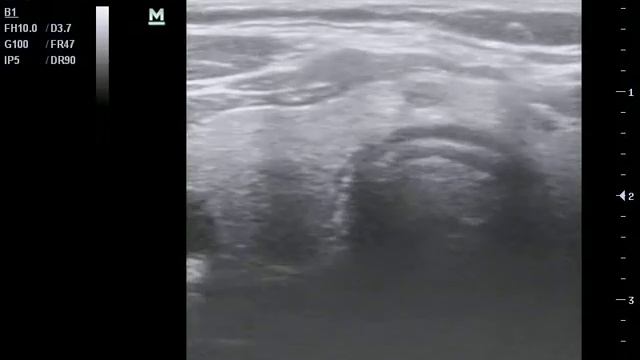

Узелковое образование что это 115 фото